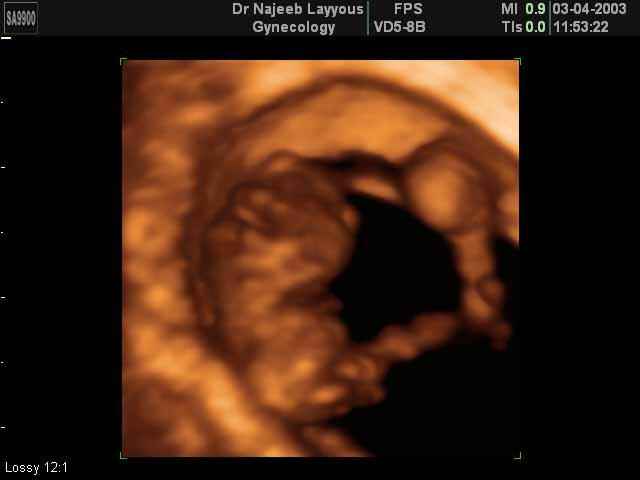

3D First Trimester Ultrasound Scan Photos